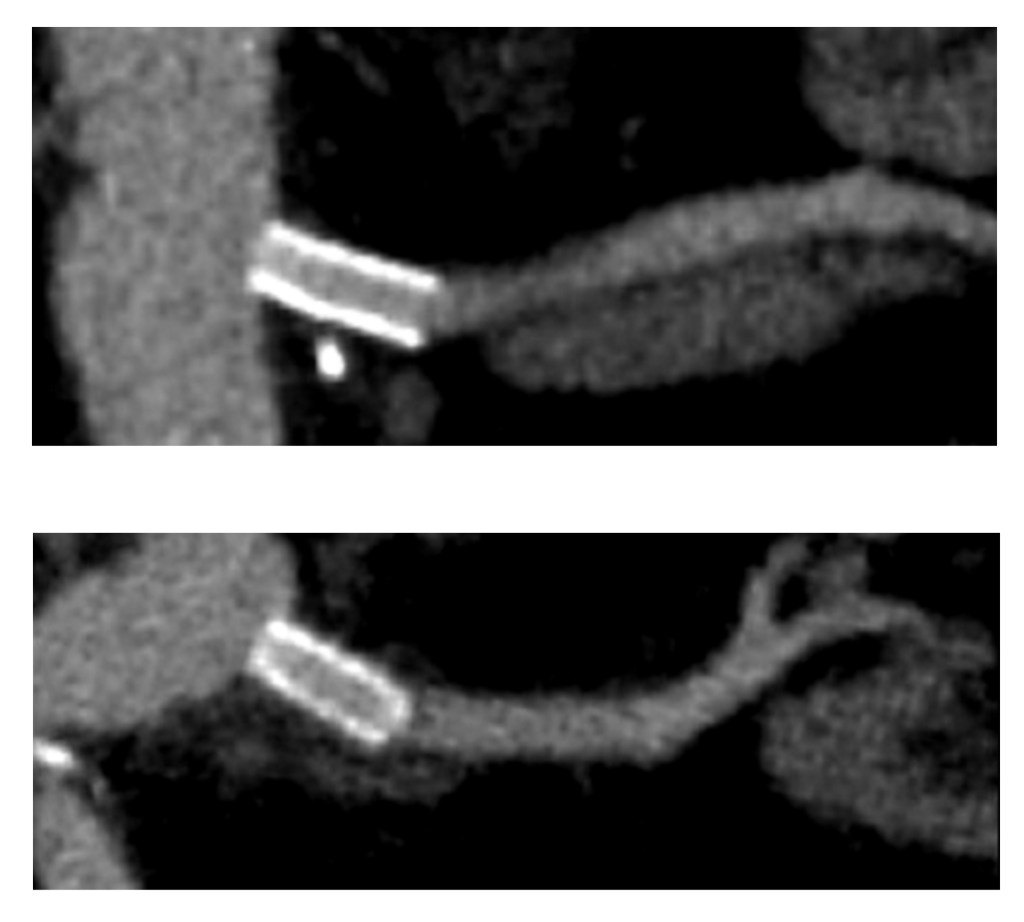

The patient’s thrombotic plaque went up to the renal origins and needed to be endarterectomized, but embarking on a renal endarterectomy adds potentially harmful renal ischemia time. Therefore, through the vertical aortotomy, I was able to get a clean end point to the aortic thromboendarterectomy and position a stent in the renal orifice and deploy it.

Once the stent was deployed, the aorta was partially closed primarily to allow the clamp to be moved below the renal arteries. This all took less than ten minutes of ischemia time. The aortic graft was then sewn end to side to the remaining aortotomy.

The patient recovered and was discharged on POD#6 with normal renal function. In followup, his CTA showed excellent graft and stent patency.

The centerline view of the renal stent shows it to be widely patent.